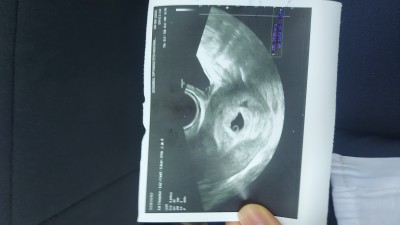

bakın kızlar yıllar sonra Rabbim nasip etti şükürler olsun

Bak içinde bebeginde var ❤️

Bebeği besleyen şeymiş o dedi doktor

Yolk kesesi onun var olması demek bebek zaten :)

Ne biliyim bebek yok henüz diyince dedim demek onun olmasını beklicez :)